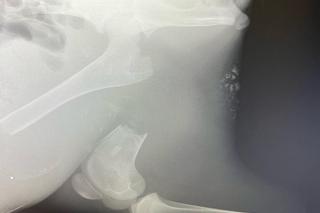

Iga to malutka łosica, która nieszczęśliwie złamała nogę. To ciągle dziecko, ale rekonstrukcja połamanej kończyny jest konieczna. Trzy nogi nie utrzymają ciężaru rosnącego zwierzęcia. Iga trafiła do Fundacji Ada w Przemyślu, gdzie zostanie przeprowadzona operacja.

- Iga ma złamaną nogę. Bez ratunku umrze. Potrzebuje natychmiastowej operacji. Nie dorośnie, nie zacznie żyć.  Iga to sierotka uratowana w województwie małopolskim. Kilka miesięcy walczyła, by móc być na świecie, jednak los spowodował, że doznała poważnego urazu. Tragiczne złamanie kości udowej. Potrzebna jest natychmiastowa operacja i kosztowne  materiały, zamawiane specjalnie pod ciało Igi. Zabieg musi być wykonywany przy asyście anestezjologa. Iga ma kilka miesięcy, czas niestety działa na niekorzyść dziecka. W nadchodzącym tygodniu odbędzie się zabieg - informują weterynarze z Lecznicy Ada.